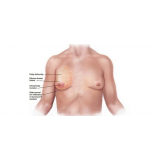

Mamoplastia de Elevação

Se você não sabe onde encontrar bons profissionais, equipe médica compromissada e sempre pronta a atender bem o seu cliente? Pois não se preocupe mais pois a FF Cirurgia Plástica coloca à disposição do cliente a possibilidade de contratar assistência médica pertinente que o possibilite submeter-se à mamoplastia de elevação.

Não pense duas vezes: conheça o consultório médico que realiza mamoplastia de elevação!

Praticidade pensada no que é mais adequado às necessidades do cliente, com profissionais de saúde por perto, levando maior segurança e eficiência até você. Busque com essa equipe todas as informações que precisa e saia satisfeito e tranquilo! Qualidade e bom atendimento você encontra de excelência na FF Cirurgia Plástica.